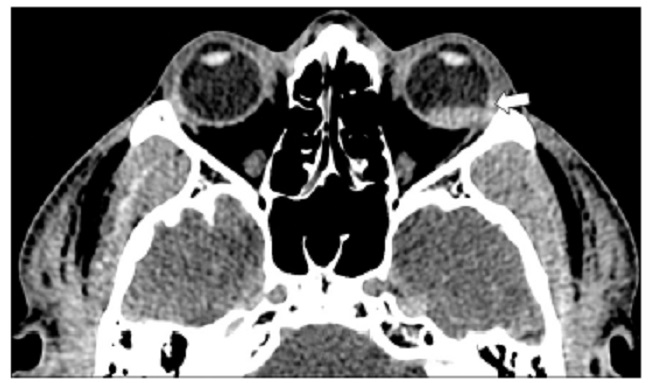

El globo ocular se localiza en la órbita anterior y corresponde a un tercio del volumen total de la órbita. La pared del globo ocular tiene tres capas: la esclerótica o capa externa, que es la capa protectora fibrosa y se continúa con la córnea en la parte anterior, es la encargada de mantener la forma y la presión del globo ocular; la úvea o capa media, que es hipervascular y contiene la coroides, el cuerpo ciliar y el iris; y la retina o capa interna, que tiene la función sensorial del ojo. La cápsula de Tenon o fascia bulbi envuelve el globo ocular y lo separa de la grasa orbitaria. Las diferentes capas del globo ocular son difíciles de diferenciar en la TC (Fig. 1), mientras que con la RM se puede diferenciar la esclera de la coroides1,2,5,6.

El cristalino es biconvexo y se conecta a la esclera por las fibras zonulares que están orientadas radialmente, dividiendo el globo ocular en segmento anterior que contiene el humor acuoso y el posterior que contiene el humor o cuerpo vítreo. El iris subdivide el segmento anterior en cámara anterior y posterior. Sin embargo, la cámara posterior no se visualiza en las imágenes debido a su pequeño tamaño. La irrigación arterial se da principalmente por la arteria oftálmica. que es rama de la arteria carótida interna, y sus principales ramas son la arteria central de la retina y las arterias ciliares posteriores. El drenaje venoso mayor ocurre por la vena oftálmica superior5.